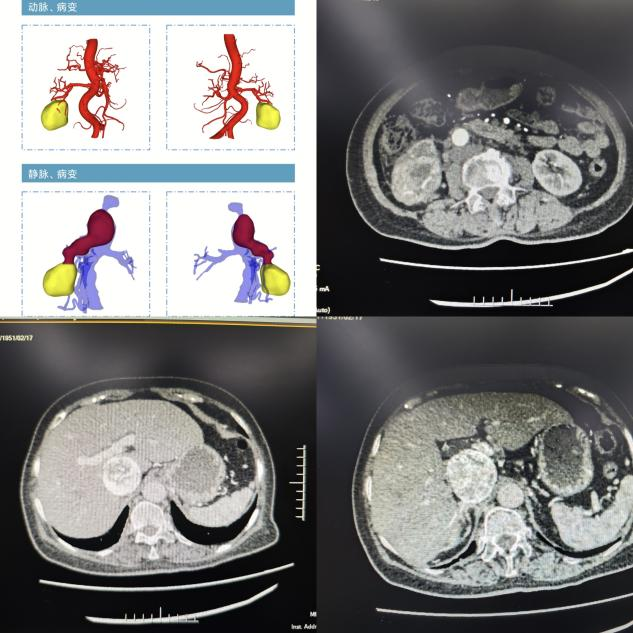

患者术前影像学检查

该患者5月前因血尿至当地医院就诊,完善B超检查发现右肾占位性病变,直径约6cm,当时未予特殊处理。1月前至当地医院复诊,MRI检查提示:右肾下极囊实性占位性病变,肿瘤沿肾门及右肾静脉向上蔓延生长,达下腔静脉旁,下腔静脉肝段受压变窄,与肿瘤分界欠清,肿瘤大小为5.8*5.3*18cm。当地医院联系樱花动漫 泌尿外科知名专家丁明霞副院长寻求帮助,丁明霞副院长了解病情后将该患者收治到医院泌尿外科一病区肾肿瘤亚专业组。随后,为全面准确地评估患者病情,由詹辉教授带领的肾肿瘤亚专业组邀请了麻醉手术科欧阳杰、肝胆胰外科田大广、放射科郭立、心脏血管外科段玉印等专家开展多学科会诊。经过讨论,专家认为该患者肿瘤增长迅速,性质倾向恶性,考虑肾透明细胞癌可能,建议行手术治疗。且相较于既往的肾恶性肿瘤切除术而言,该患者肿瘤与下腔静脉、双肾静脉关系密切,结合术前影像学分析,瘤栓已接近肝静脉平面,手术取栓难度极大、出血风险极高。

术中,见肿瘤位于患者右侧肾脏,整体呈类圆形状,大小约6*6*5cm。肿瘤与下腔静脉关系密切,侵及右肾静脉及下腔静脉,瘤栓上极超过肝短静脉水平。在充分剥离肿瘤及血管的基础上,切除上至肝短静脉上缘下达双肾静脉以下约1cm的下腔静脉、右肾静脉,并夹闭左肾静脉,将瘤栓完整取出。